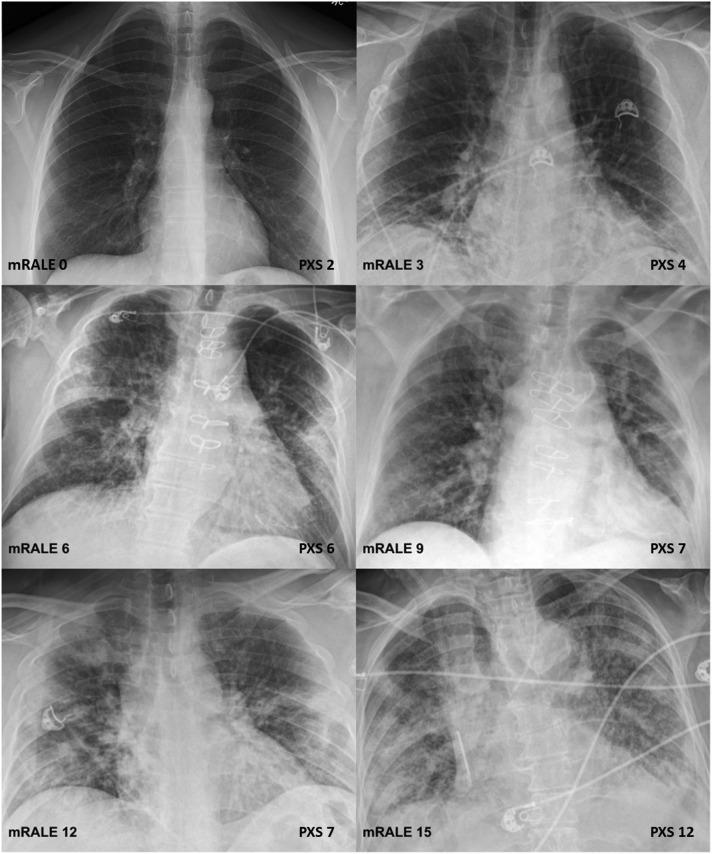

An externally developed deep learning model for COVID-19 radiographic lung disease severity assessment was loaded into the AI-LAB platform at an independent academic medical center, which was separate from the institution in which the model was trained. The data set consisted of CXR images from 141 patients with reverse transcription-polymerase chain reaction-confirmed COVID-19, which were routed to AI-LAB for model inference. The model calculated a Pulmonary X-ray Severity (PXS) score for each image. This score was correlated with the average of a radiologist-based assessment of severity, the modified Radiographic Assessment of Lung Edema score, independently interpreted by three radiologists. The associations between the PXS score and patient admission and intubation or death were assessed.

The PXS score deployed in AI-LAB correlated with the radiologist-determined modified Radiographic Assessment of Lung Edema score (r = 0.80). PXS score was significantly higher in patients who were admitted (4.0 versus 1.3, P < .001) or intubated or died within 3 days (5.5 versus 3.3, P = .001).